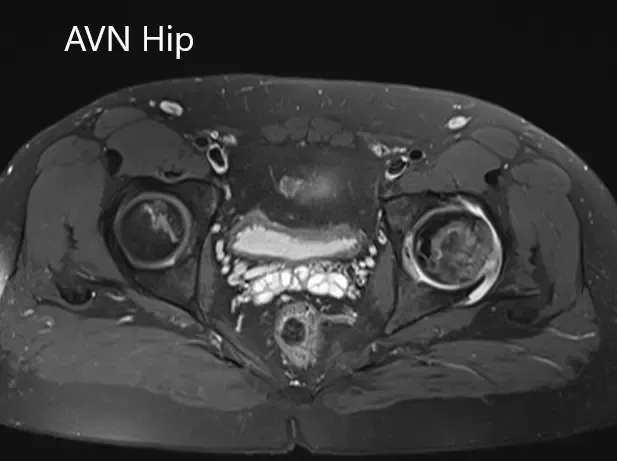

Imaging studies obtained in the form of an X-Ray suggested sclerosis of the left head of the femur. There were marked acetabulum changes. An MRI was further obtained suggesting avascular necrosis of the superior lateral head of the femur with changes in the acetabulum. There was marked hypointense areas on both T1WI and T2WIs.

Axial sections of the T1WI and T2WI of MRI.